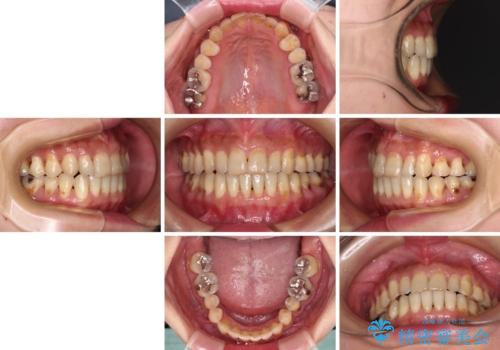

- 歯列不正と、どこで咬んで良いのか分からない咬み合わせを気にして来院された患者様です。

下顎骨は左側にシフトしており、咬み合ったときには奥歯と前歯の一部しか接触していない状態でした。

骨格的な左右差は歯列矯正は改善できないため、上下歯列が全体的に接触することをゴールとしてインビザラインにて矯正治療を行うこととしました。

マウスピース矯正は、奥歯が常にマウスピースを介して咬み合うため、治療過程において前歯のみが接触して奥歯が咬み合わないということが頻発します。

元々奥歯の咬み合わせに問題のある方の場合、治療期間が長期化したり、咬み合わせの改善ができなかったりすることがあります。

マウスピースのみでは治療を終了させることができなくなり、ワイヤー矯正を併用したり、顎間ゴムを多用したりといった対応が必要となります。